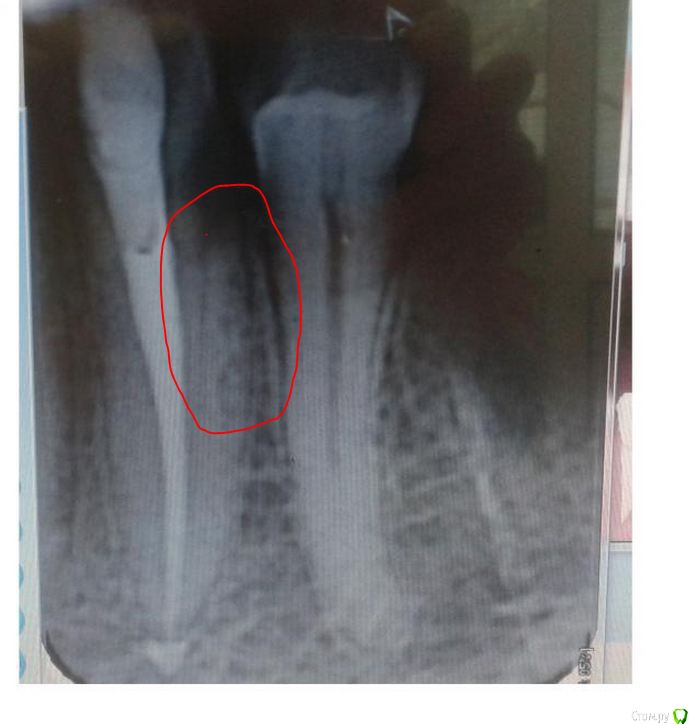

St. Опубликовано 24 августа, 2015 Поделиться Опубликовано 24 августа, 2015 (изменено) Если Вы об этом - то это не канал , а контуры костной перегородки между этим и соседним зубом. А снимки выкладывайте, посмотрим. Изменено 24 августа, 2015 пользователем St. Ссылка на комментарий

mariskus71 Опубликовано 25 августа, 2015 Автор Поделиться Опубликовано 25 августа, 2015 (изменено) Если Вы об этом - то это не канал , а контуры костной перегородки между этим и соседним зубом. А снимки выкладывайте, посмотрим.Спасибо Вам большое,сняли груз с души,а то я уж думала,что дополнительный канал не запломбировали.Выкладываю снимки.Первый снимок был сделан после пломбировки временным каласептом.Второй перед пломбировкой прошли канал и нашли дополнительный.А на последнем врач отметил непонятные участки (со вторым я поняла,а вот с первой цифоркой то же непонятно)Спасибо Изменено 25 августа, 2015 пользователем mariskus71 Ссылка на комментарий

St. Опубликовано 25 августа, 2015 Поделиться Опубликовано 25 августа, 2015 Пожалуйста) По снимку с инструментами всё хорошо. По тому который после пломбировки - тоже.Что врач хотел отметить - не знаю.Как сейчас ведет себя зуб? Неприятные ощущения уменьшаются? Ссылка на комментарий

St. Опубликовано 26 августа, 2015 Поделиться Опубликовано 26 августа, 2015 По поводу морального состояния Вам правильно сказали. Я думаю всё будет хорошо. Через пол года сделайте контрольный снимок чтобы убедиться.Между материалам в канале и верхней пломбой может быть неконтрасный материал, так что с этим всё ок. Что доктор сказал по поводу дальней поверхности этого зуба по снимку похоже что там кариес? Ссылка на комментарий

mariskus71 Опубликовано 26 августа, 2015 Автор Поделиться Опубликовано 26 августа, 2015 По поводу морального состояния Вам правильно сказали. Я думаю всё будет хорошо. Через пол года сделайте контрольный снимок чтобы убедиться.Между материалам в канале и верхней пломбой может быть неконтрасный материал, так что с этим всё ок. Что доктор сказал по поводу дальней поверхности этого зуба по снимку похоже что там кариес?Если Вы имеете ввиду затемнение на снимке справа,когда делали первый снимок,это затемнение и было объектом внимания и первой причиной депульпирования,так как затемнение практически подходит к каналу зуба.На снимке видно затемнение,а при осмотре ничего.Проходили зондом,на температурные раздражители и воздух зуб не реагировал,делали снимок с небольшим кусочком гуттаперчи,который закладывали под десну- на этом снимке мне показали,что гуттаперча лежит на месте затемнения,но там зондом ни чего не определяется.Врач сказал,что может под десной глубже. Скажите,а вот если зуб при накусывании не болит, а если стучать по нему то больно,это плохо?Или в моём случае это пока может быть? А можно вопрос несвязанный с этим зубом.У меня на зубе от ношения бюгельного протеза(который я уже не ношу)образовался дефект(небольшая дырочка)можно ли её закрыть,не меняя всю пломбу или пломбу нужно всю высверливать и ставить новую(уж больно стенки тонкие)Спасибо. Ссылка на комментарий